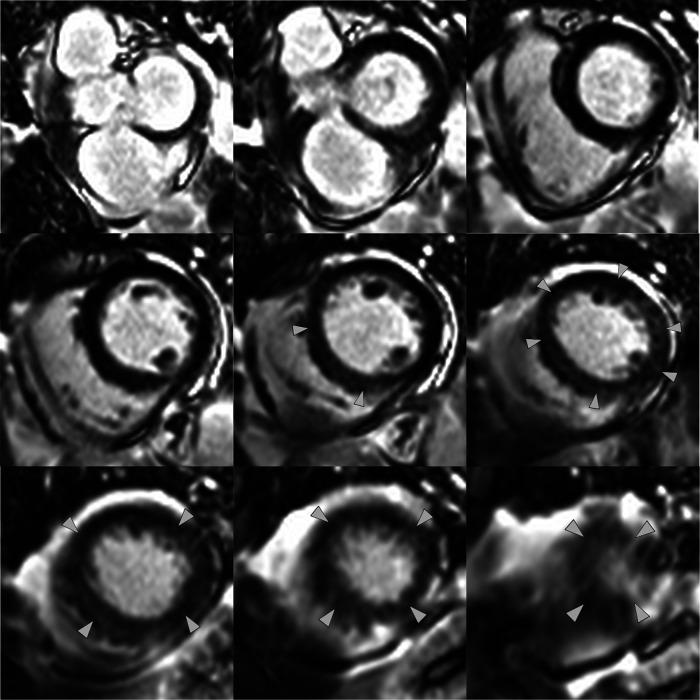

A 69-year-old lady was admitted with chest pain and shortness of breath. She was found to have classical TTS with the characteristic wall motion abnormalities on echocardiogram, left ventricular angiogram, and CMR. Her CMR also demonstrated strongly positive myocardial T/T mapping that matched the wall motion abnormalities and the less frequently described positive early and late gadolinium enhancement.

一名69岁女性因胸痛和气短入院。经超声心动图、左心室血管造影和CMR检查,发现她患有典型的TTS,伴有特征性的室壁运动异常。她的CMR检查还显示心肌T/T映射呈强阳性,与室壁运动异常相符,且有较少被描述的早期和延迟钆增强阳性表现。